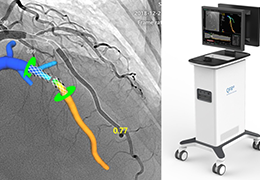

工作流智能。

在这里,先进的智能功能自动执行手动任务和工作流程步骤,以简化流程,提高技术人员工作效率,节省时间和金钱,并增强患者护理。

自动化设备定位和患者姿势确认可优化放射科技师的效率并加快工作流程。

自动技术选择可改善影像一致性并支持辐射剂量控制。

通过任务自动化功能改进感染控制,使放射科技师不再与潜在感染患者直接接触。